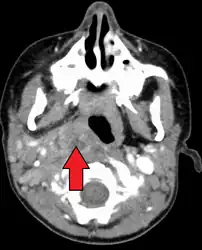

A computed tomography (CT) scan is the definitive diagnostic imaging test.[6]

Large retropharyngeal abscess as seen on CT -

Large retropharyngeal abscess as seen on CT